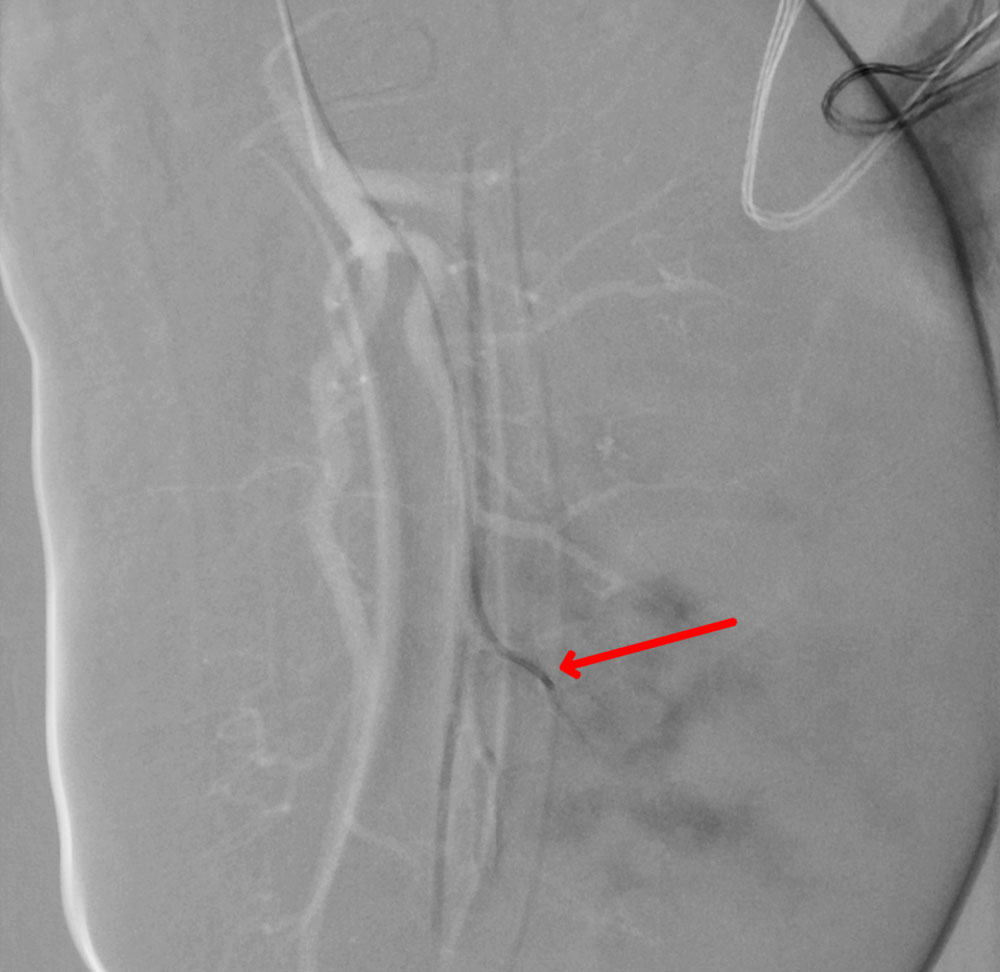

Die interventionell-radiologische, perkutane, transarterielle Embolisationstherapie des KHE/TA mit dem Ziel einer zumindest teilweisen Devaskularisation stellt gerade auch in der klinisch schwierigen Gerinnungssituation eines Kasabach-Merritt-Phänomens eine gute invasive Alternative dar. Durch die interventionelle Devaskularisation kommt es direkt zu einer deutlich geringeren Thrombozytenaktivierung durch den verminderten oder teilweise je nach Radikalität der Embolisation dann ganz fehlenden Kontakt der Thrombozyten mit dem pathologischen Tumorgefäßendothel. Die Gerinnungsparameter können sich bereits 24 Stunden nach der Embolisation massiv verbessern. Durchgeführt wird diese Embolisation meist als Partikelembolisation über Mikrokatheter unter prophylaktischer Antikoagulation. Spezielle Kenntnisse in der pädiatrisch-interventionellen Radiologie sind hier bei den Säuglingen hilfreich, der Eingriff ist entsprechend erfahrenen interdisziplinären Zentren in der Zusammenarbeit von interventioneller Radiologie, Pädiatrie, Kinderchirurgie und Anästhesie vorbehalten.